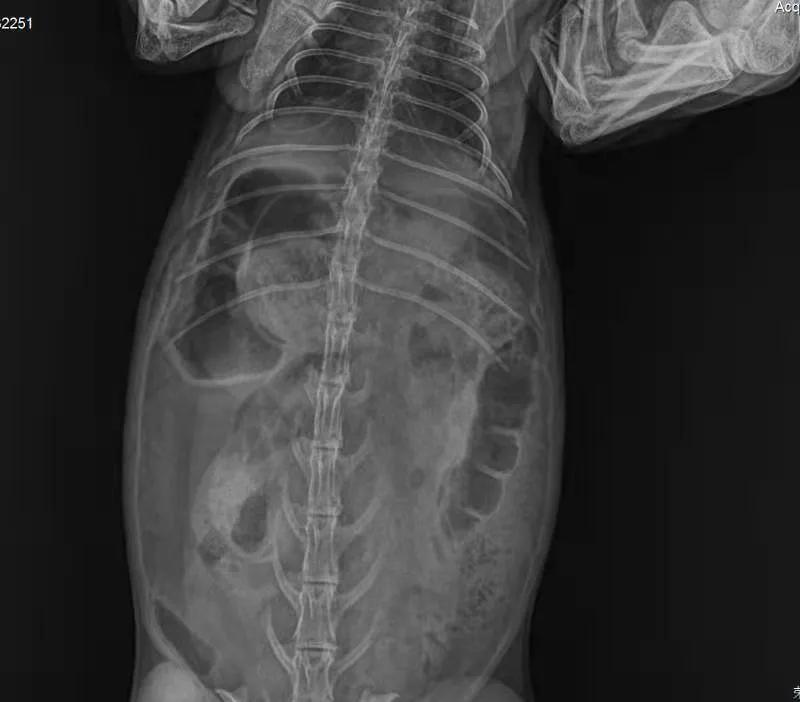

没有犹豫,立刻带它到当地动物诊所拍片,

医生看出来是胀气

表示对治疗兔子并不在行,教我怎么按摩它的肚子。我就坐在诊所帮“汤圆”按摩腹部,那是第一次“汤圆”在我身上趴那么久,它平时太凶悍了,连抓都很难抓到,从来没有一次在我怀里安稳呆过5秒钟。半小时后我要求再次拍片,显示气体有所移动。